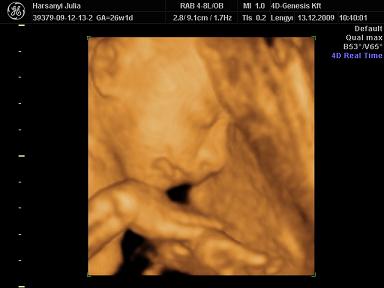

Reggel 10-re mentünk a genesisbe UH-ra. Szuper volt! :) Persze Szonja megint szégyenlősködött, és az arcát nem akarta annyira mutatni, de azért sikerült egy picit elkapni. De amit művelt, ez fantasztikus volt! Tudni kell a családunkról, hogy nálunk mindenki kéjenc, ami annyit jelent, hogy mindenkit egyfolytában simogatni, masszírozni kell (kutyát macskát beleértve, de főleg páromat meg engem). Na, a kislányunk sem hazudtolta meg a vérét, ő is ilyen! Befeküdt az UH fejnek háttal, és kifejezetten lehetett rajta látni, hogy nyomja a kis hátát meg fenekét, attól függően hogy hol szeretné magát massziroztatni. Teljesen ellazult, volt, hogy be is aludt, annyira édes volt :) A szonográfus nőnek is nagyon tetszett :) Azt mondta, teljesen tökéletes, gyönyörű baba, és természetesen mi is így láttuk :) A mérete pont a korának megfelelő, 850g, a talpacskája már majdnem 5 cm :) Ha így haladunk, akkor teljesen jó súllyal (3300 gr) fog születni.

Julcsi,teszel fel 4D fotókat Szonjáról a kis kéjenckédről? :)

Na próbálok feltenni képet a kis Tündérről: